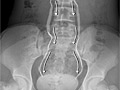

Intravenous Pyelogram (IVP)Skip to the navigationTest OverviewAn intravenous pyelogram (IVP)

X-ray test that provides pictures of the kidneys, the

bladder, the

ureters, and the

urethra (urinary tract). An IVP

can show the size, shape, and position of the urinary tract, and it can

evaluate the collecting system inside the kidneys. During IVP, a

dye called

contrast material is injected into a vein in your arm.

A series of X-ray pictures is then taken at timed intervals. IVP